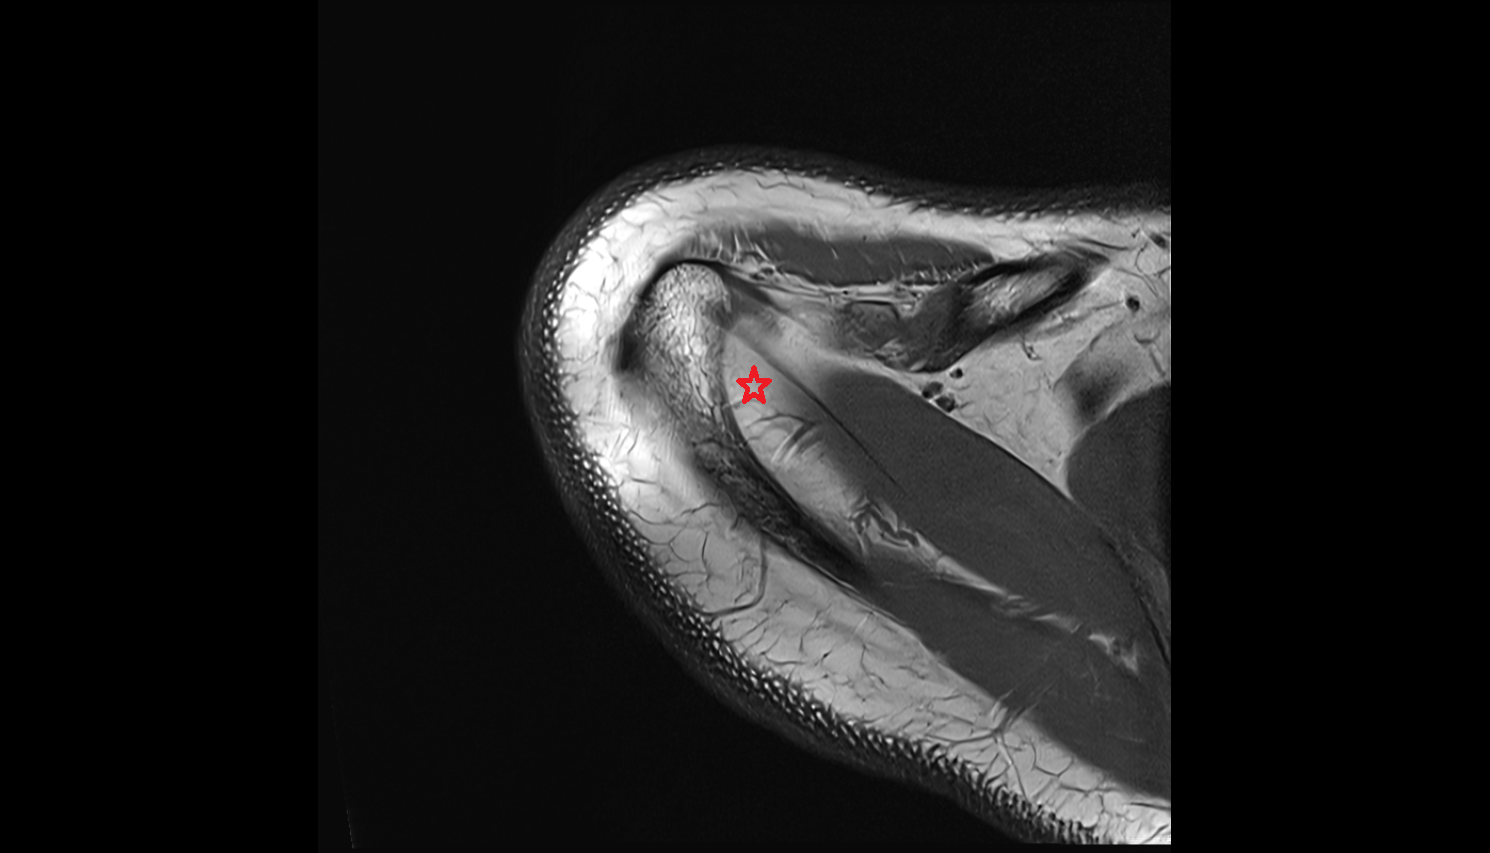

- Glenoid labrum